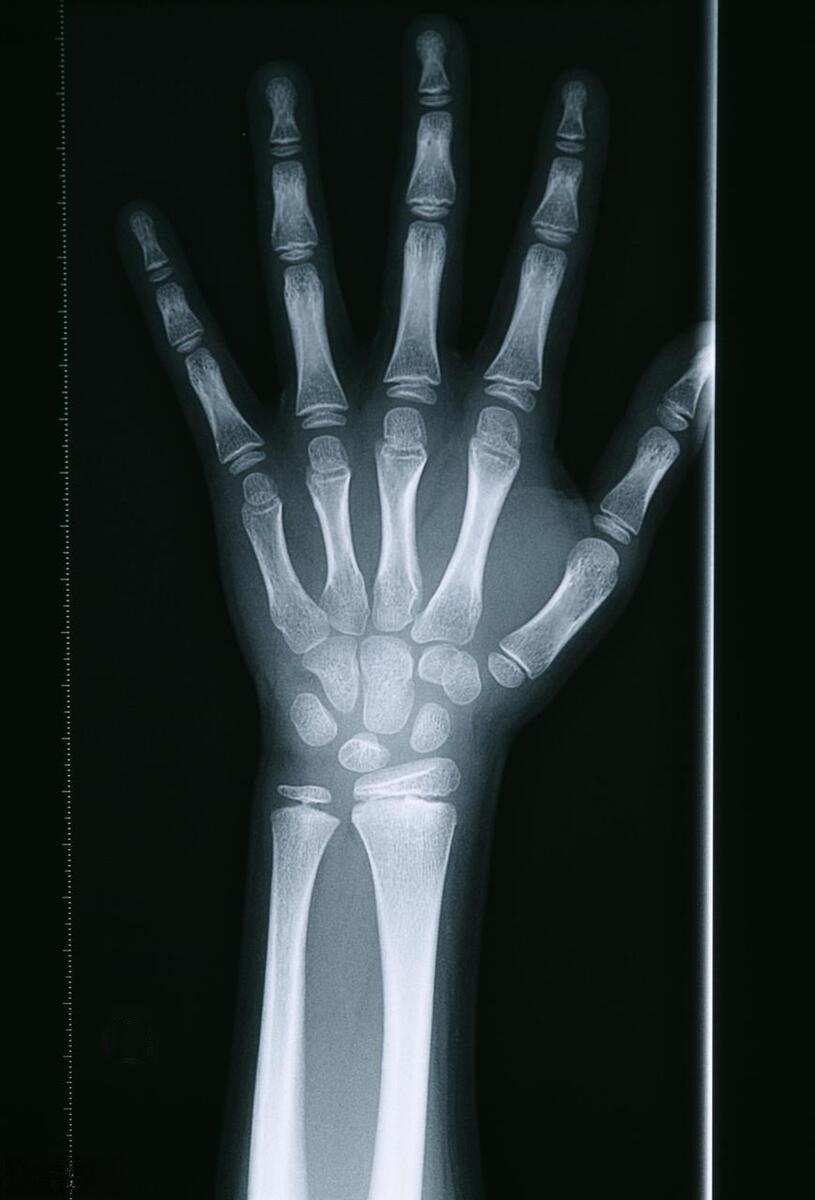

事实上,骨龄预测并非万能的。 骨龄,即骨骼的年龄,是通过X光片观察手腕部骨骼的发育程度来评估的。 它确实能在一定程度上反映儿童的生长潜力,但并不能完全决定最终身高。天津医科大学总医院儿科主任医师郑荣秀指出:“虽然骨龄的提前和落后可能会影响儿童最终的身高,但只根据一次骨龄结果判定成年身高是不准确也不科学的。”